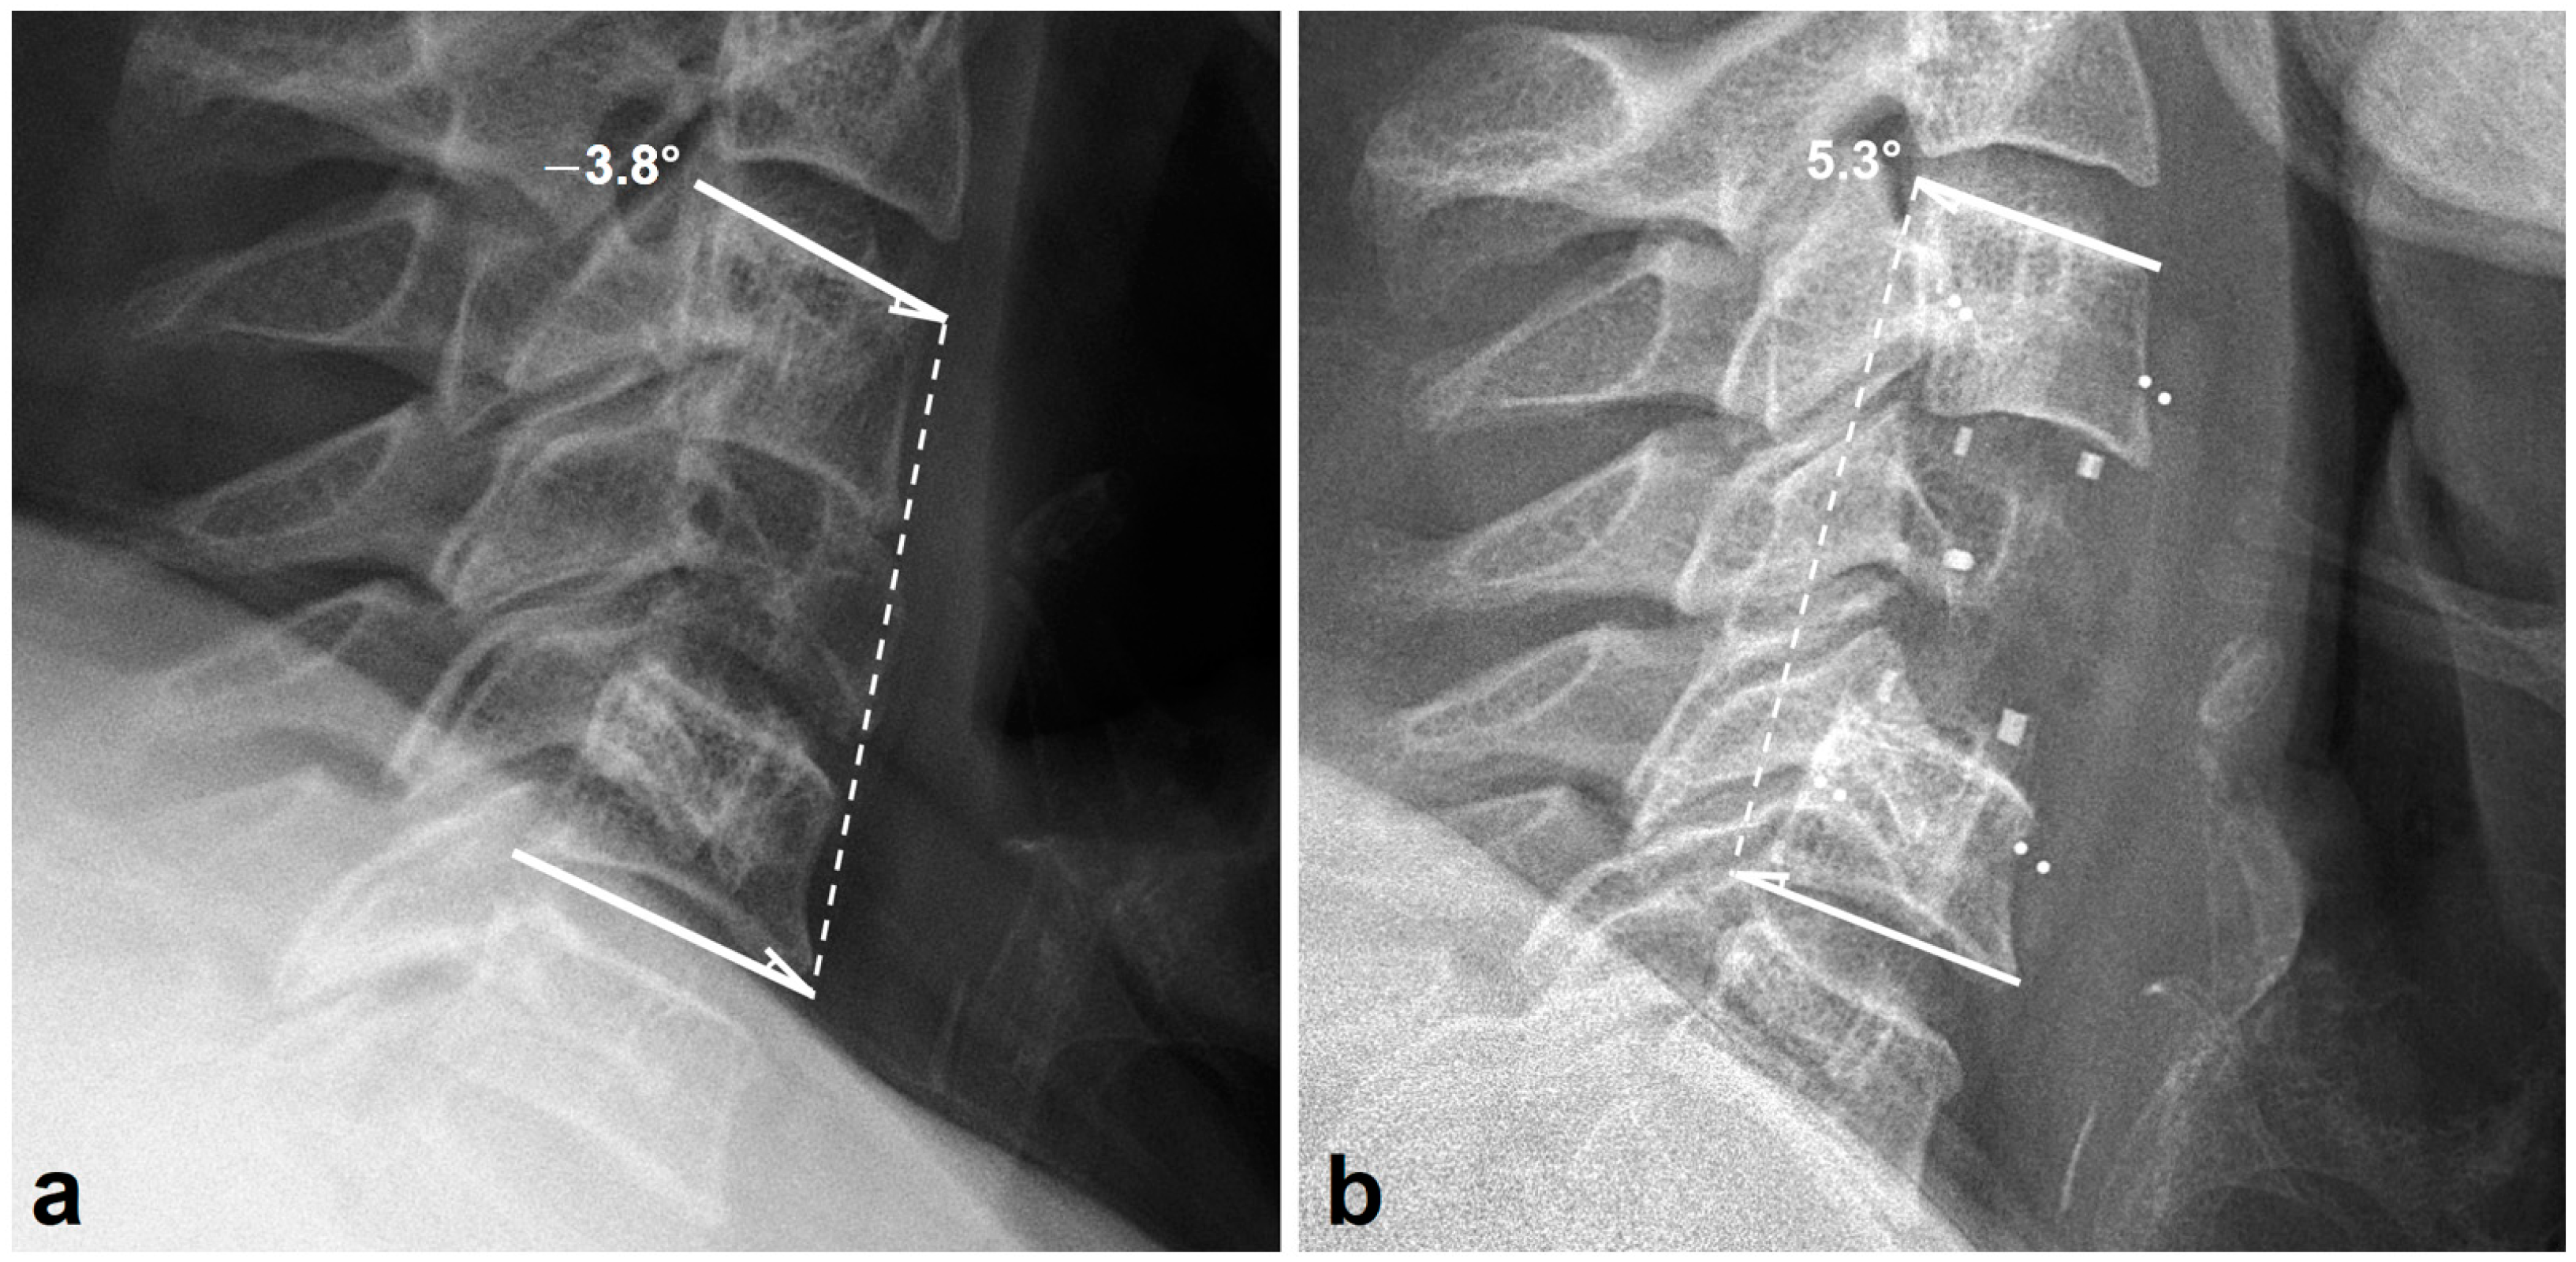

3.2. Radiologic Outcomes